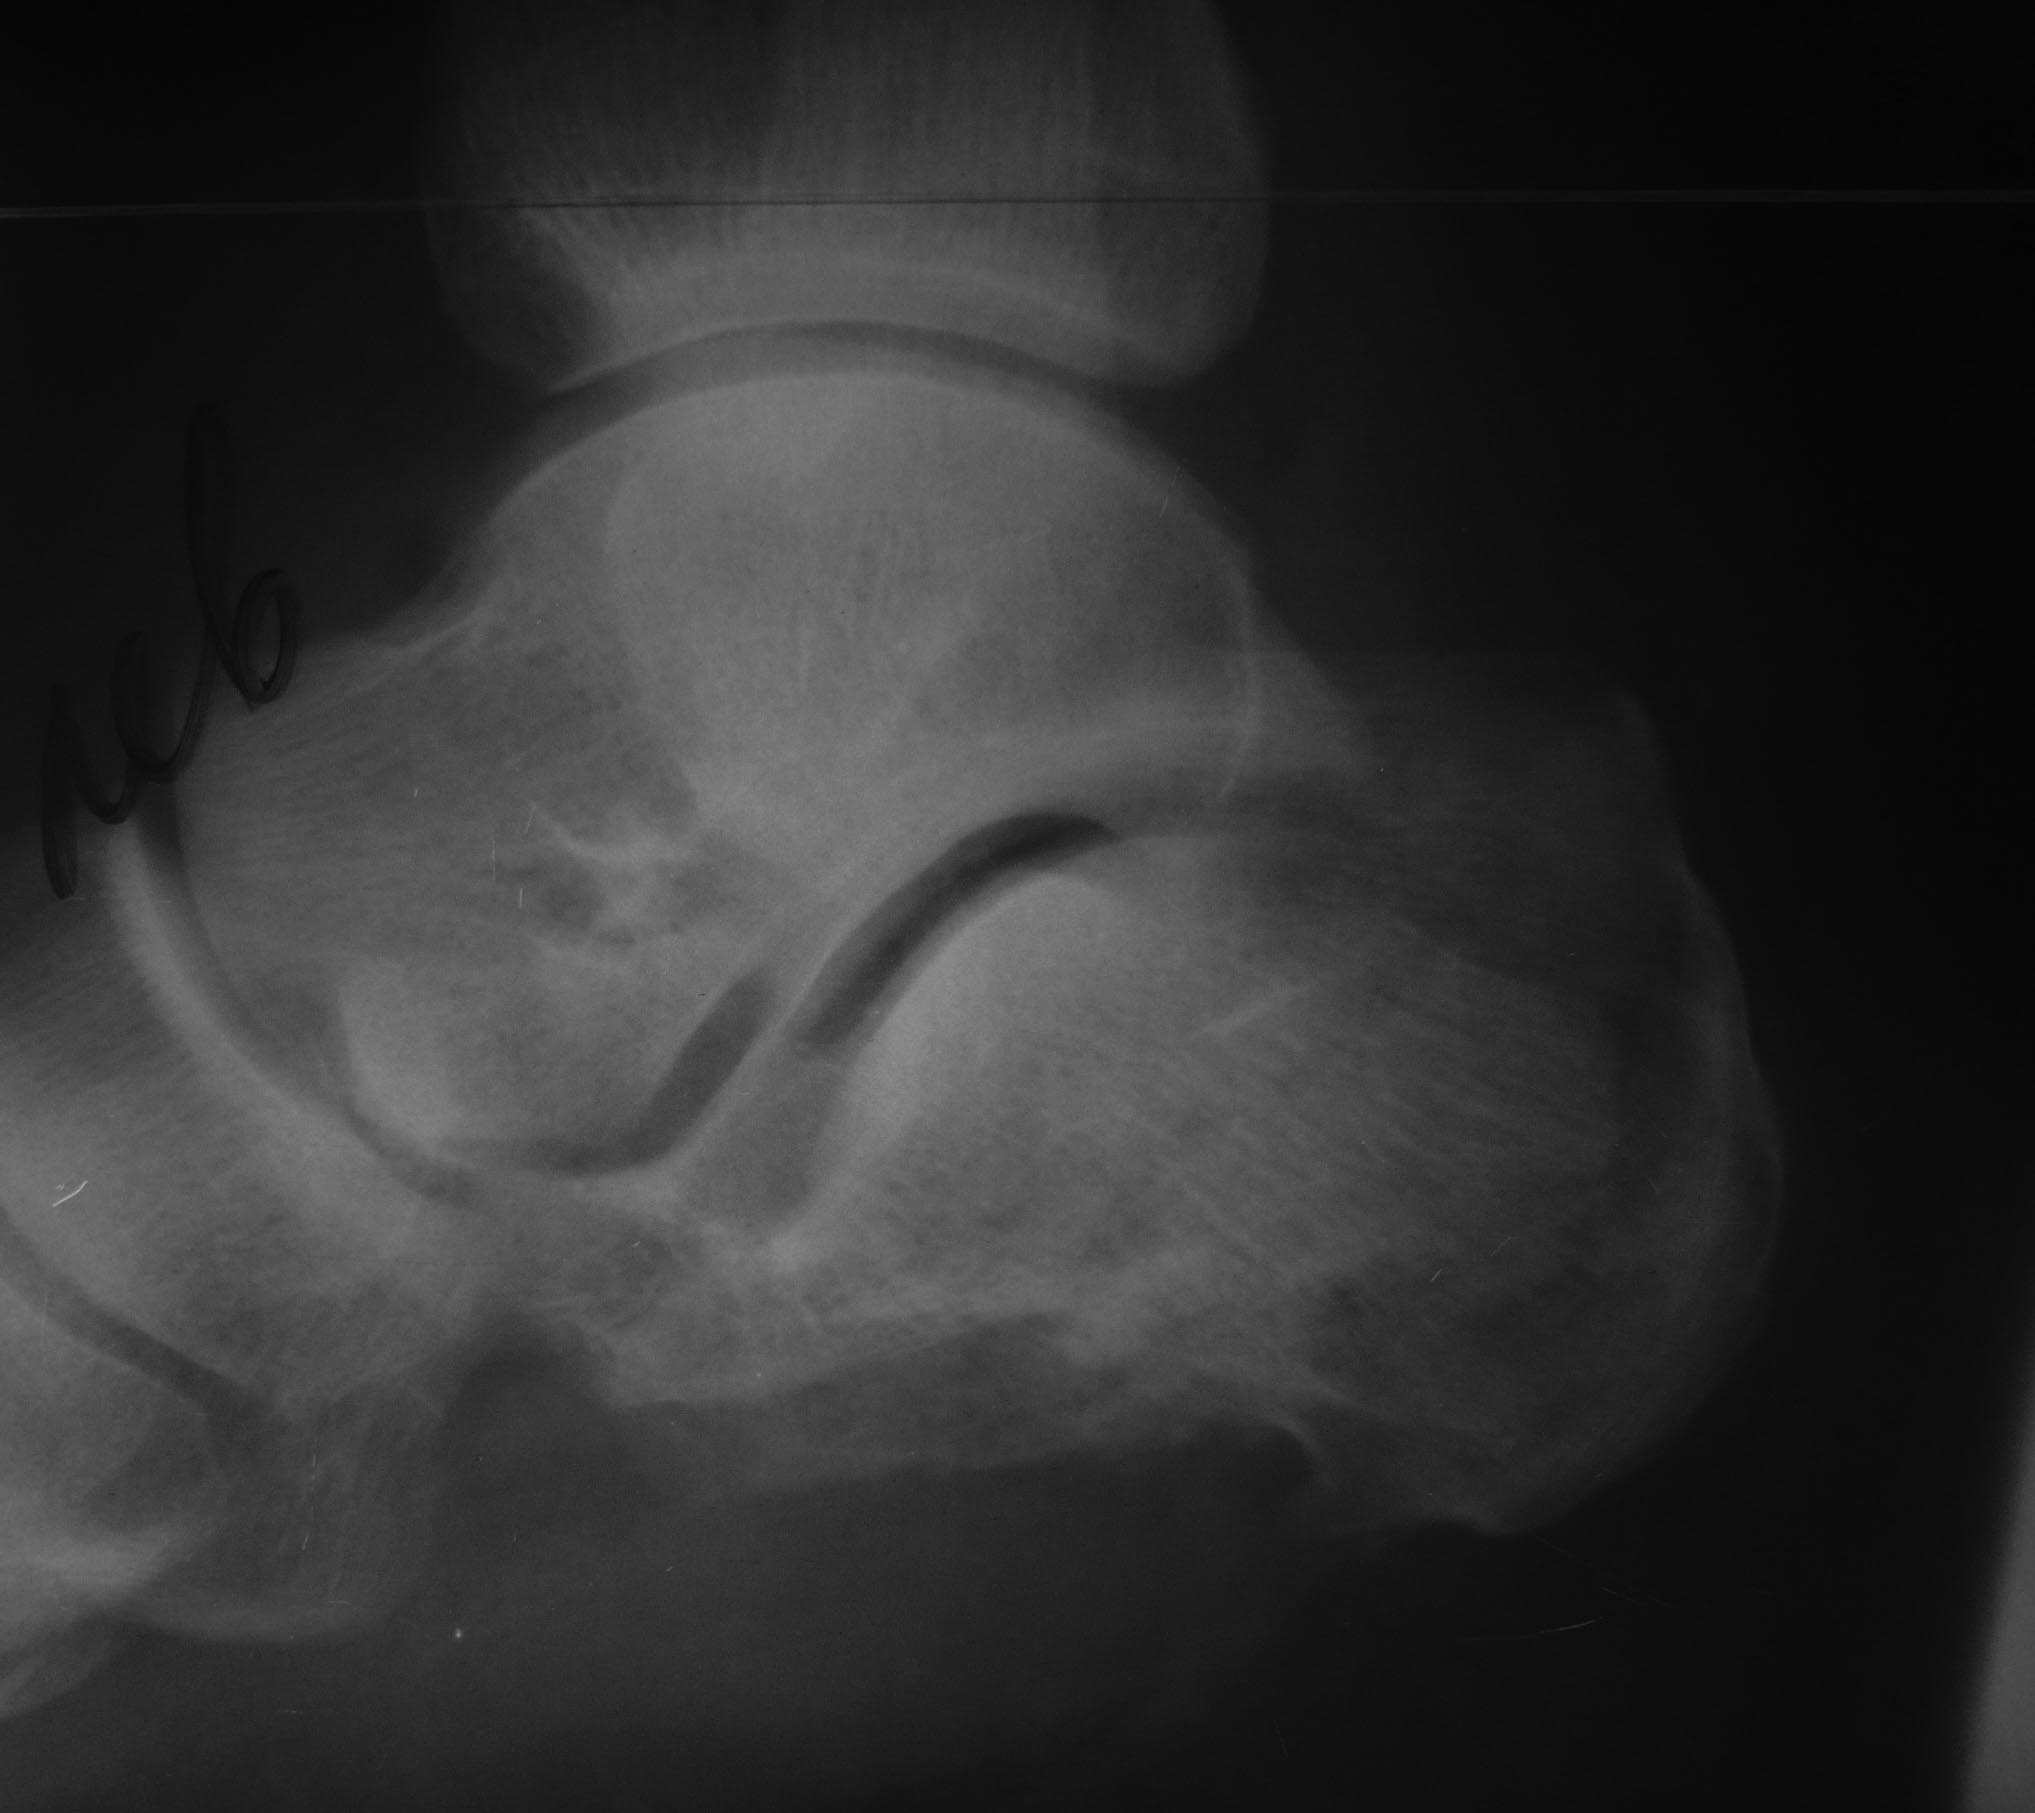

наружная лодыжка целая. Хотелось бы устранить оставшуюся импрессию суставной фасетки и еще низвести бугор из доступа в проекции подтаранного сустава, чтобы в последующем избежать уплощения свода. Мягкие ткани снаружи интактны, но в области раны с медиальной стороны сохраняется небольшое количество геморрагического отделяемого.

Пациента прооперировал 5 мая. Произвел аутопластику костной крошкой и фиксацию спицами. Выкладываю снимки

Всем привет!Изначально было желание ничего не трогать,заживить,срастить и потом устранить то что беспокоило бы пациента а это вожможно корригирующие остетомии,декомпрессия подлодыжечного пространства и уж совсем край подтаранный дез.Сейчас добра думаю не получилось как заживать будет пластика, пятка укоротилась а это и свод и размер.С уважением!